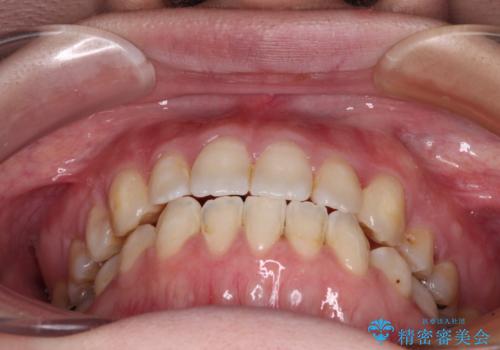

- 左上の八重歯と前歯のデコボコを気にして来院された患者様です。

下顎が左側にズレており、下顎前歯は1歯欠損していたため、左上小臼歯1本を抜歯し、ワイヤー装置にて矯正治療を行うこととしました。

骨格のズレと歯の欠損があったため、仕上がりの調整に時間がかかると思いましたが、舌突出癖の改善や顎間ゴムの装着をしっかりと行ってくださったので、速やかに治療を終えることができました。